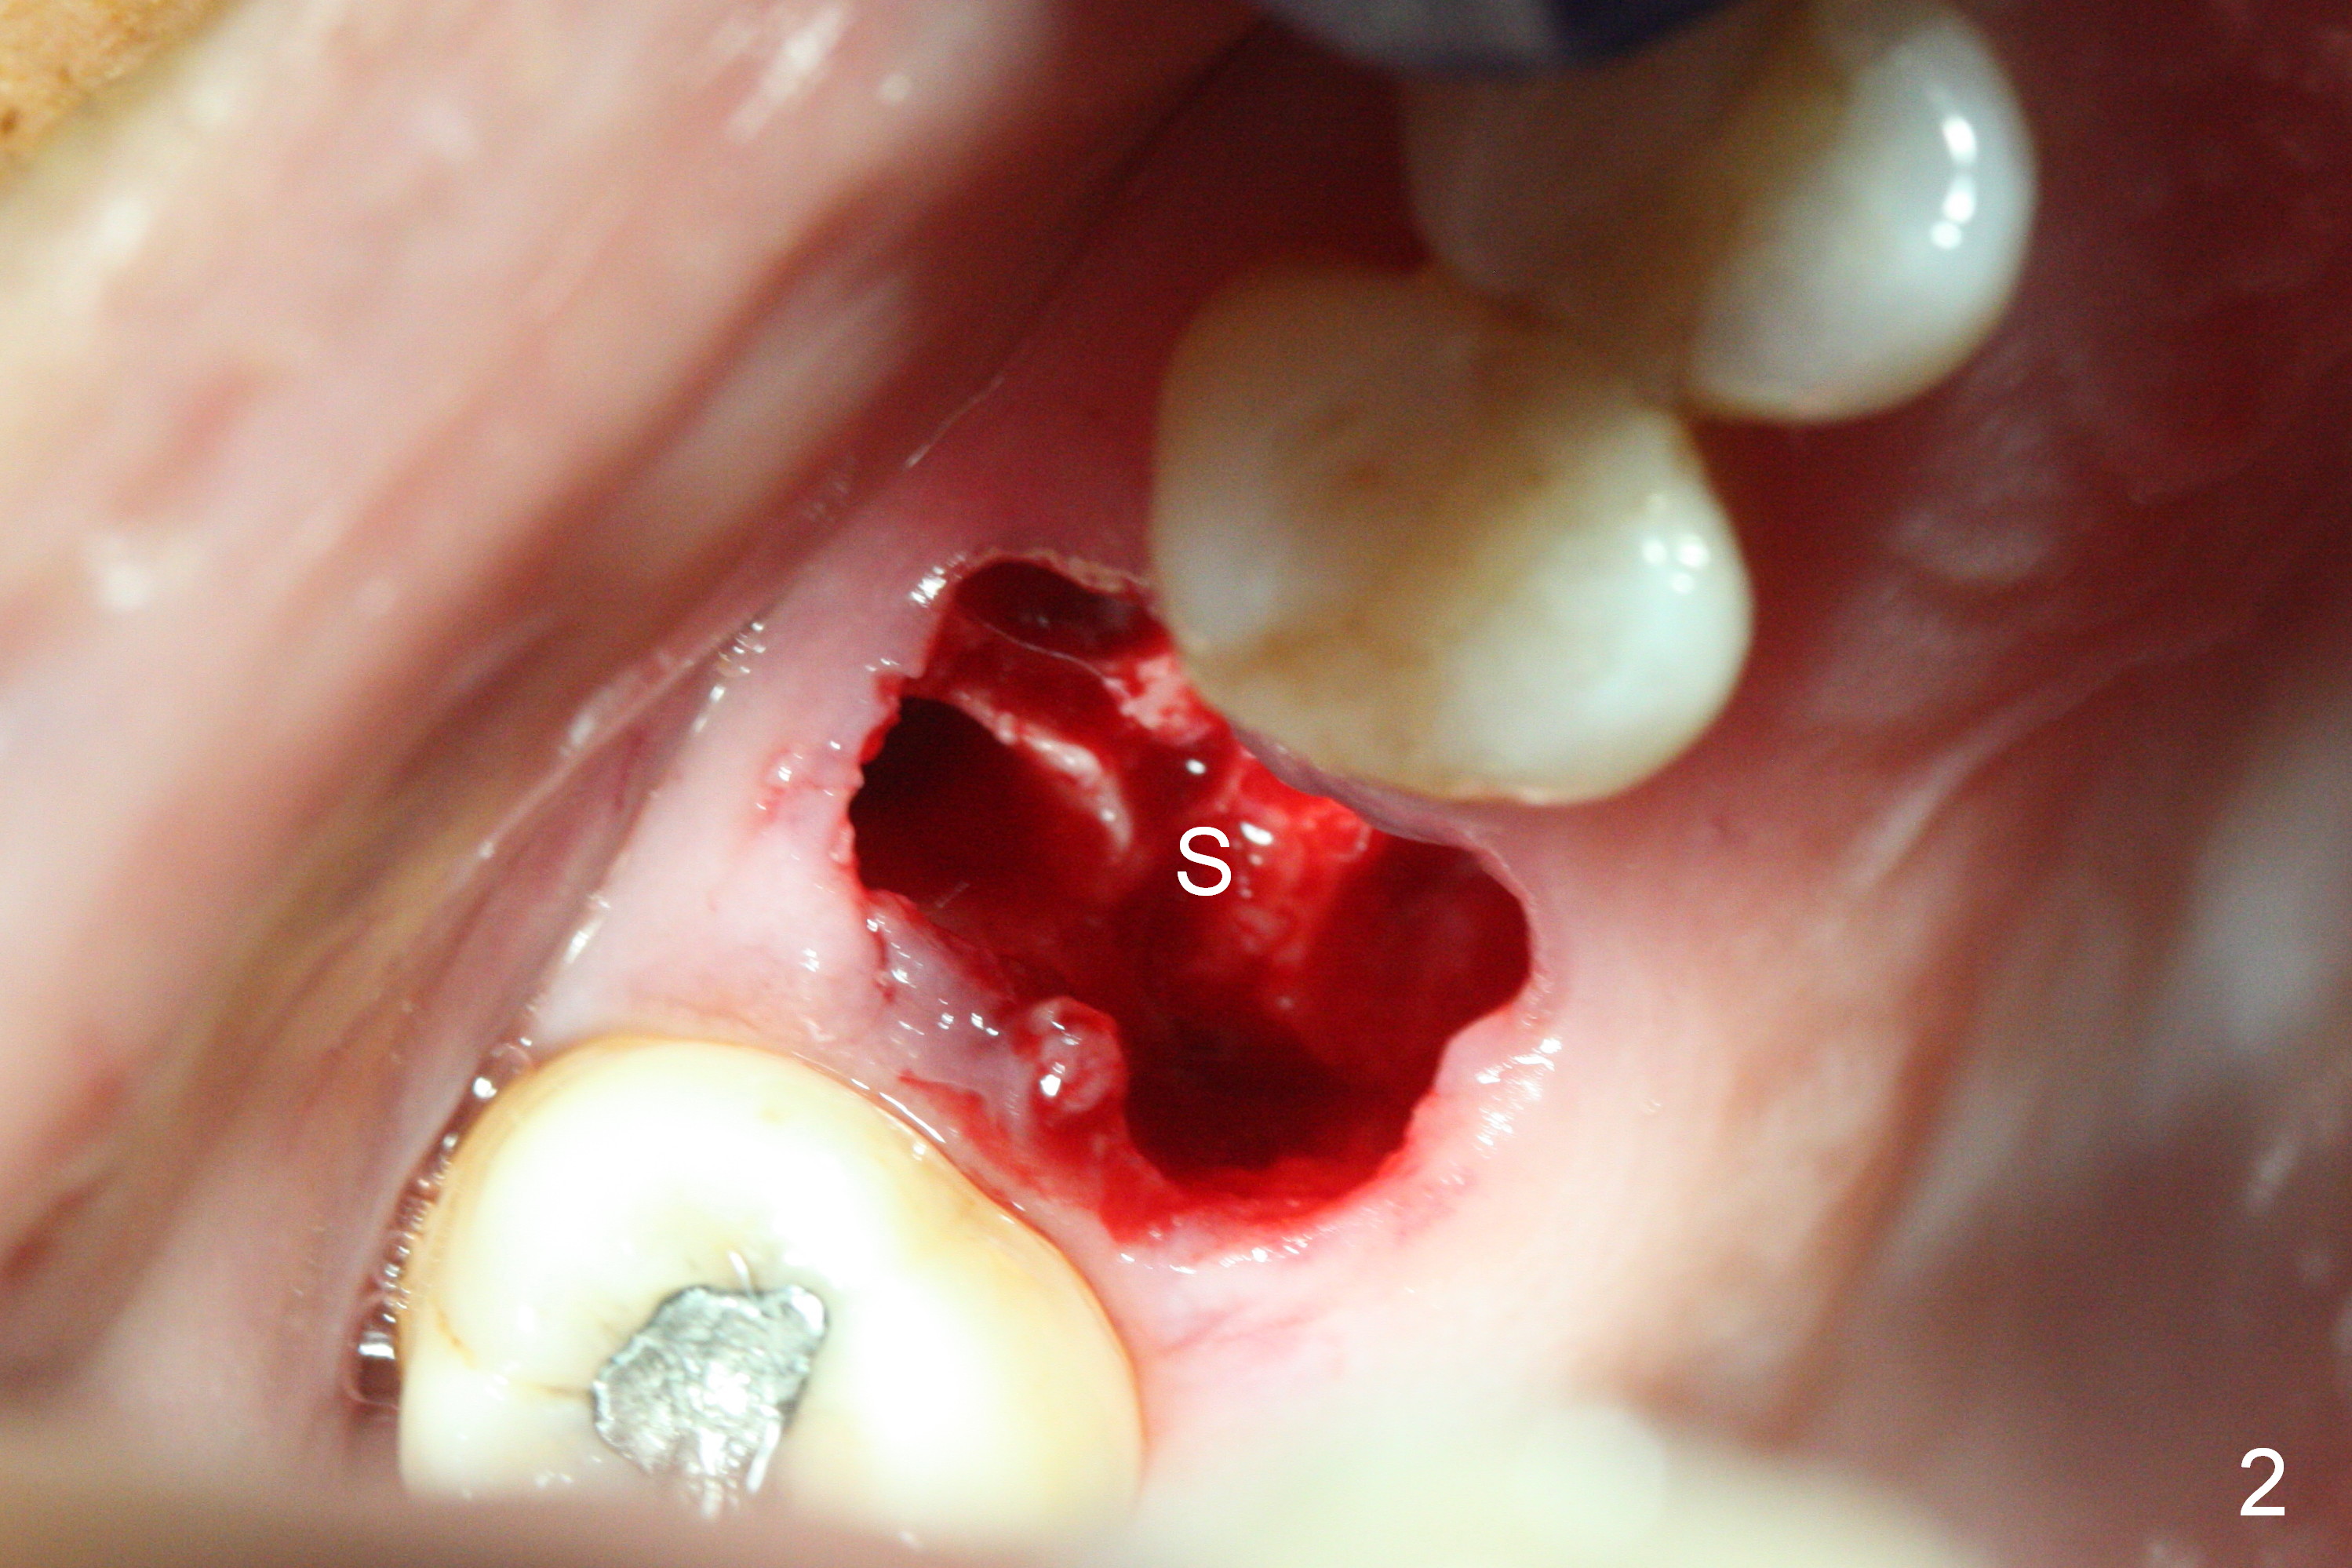

The polyp in the pulpal chamber of the tooth #3 (Fig.1) originates from the distal gingiva. After extraction, buccal plate perforation is found apical to the distobuccal socket. The septum is large (Fig.2 S). Osteotomy is initiated in the middle of the septum with 1.6 mm drill until 3.8 mm Magic Drill (MD) (Fig.3). The last drill is 4.3 mm, followed by 4.8 mm Magic Expander since the palatal wall of the osteotomy is thin after the last drill. A 5x13 mm IBS implant is placed with ~ 45 Ncm. The apical portion of the 3 sockets is filled with Osteogen plug and the coronal portion with autogenous bone (harvested from MD), mixed with allograft and Osteogen (Fig.4 * as well as collagen plug in the most superficial portion of the sockets). A 6.5x4(4) mm pair abutment (Fig.4 A) is placed to hold an immediate provisional in place.